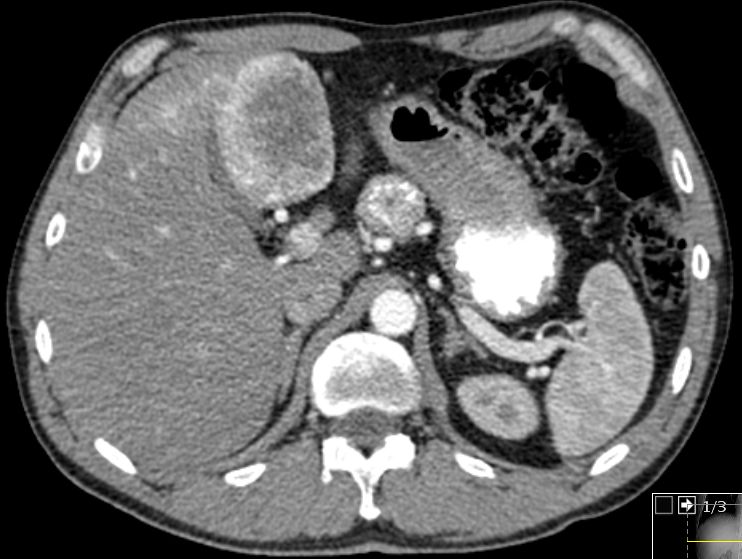

Intrahepatisch Nachweis mehrerer, insbesondere in

der arteriellen Phase stark Kontrastmittel aufnehmender tumoröser

Raumforderungen. Lymphknotenmetastase hinter der Magenwand.![]() |